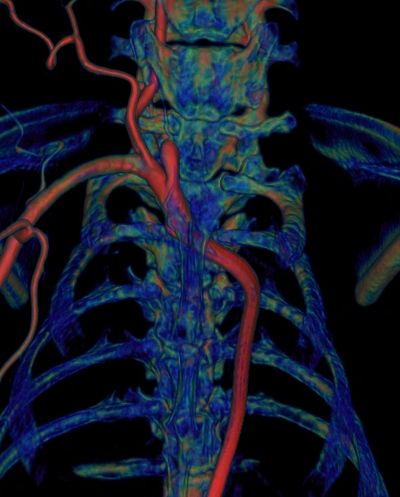

Vascular phantoms are a very important tool for benchtop testing of new devices and procedure. 3D printing offers a great opportunity to create testing settings very similar to the clinical situations. Using our 3D printing facility we created a plethora of patient specific arterial geometries based on CT, MRI or CBCT from patient data. Patient data acquired using various imaging modalities is loaded into a 3D station for 3D rendering and processing. We manually select the vessel of interest and perform a dynamic vessel growing and export the geometry as 3D meshes in a Stereo-Lithographic (STL) File, which will be uploaded in a mesh manipulation software. Using this software we manipulate the model to merge outlets and support in order to make a friendly benchtop model. We created full Circle of Willis models, aneurysm models, cardiac models and aortic arch models. These models can be interconnected and attached to a pump to simulate physiological flow. We use these models to simulate ischemic stroke and treatment, aneurysm treatment and diagnosis.